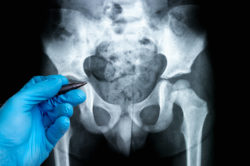

Patient Says ASR Metal On Metal Hip Replacement Has Defective DesignA patient says that the design of the ASR metal on metal hip replacement is defective and can cause adverse side effects.

Shawn is one of many patients who take issue with the design of the ASR metal on metal hip replacement. Shawn states that the ASR hip replacement is made with two main components — a ball of the hip and a socket of the hip. He says that in most hip replacement devices, one component is made of metal while the other is made of plastic, so no metal rubs directly on metal.

Shawn argues that in the case of the ASR hip, both the ball and the socket are made of metal, and if the two pieces are not implanted at exactly the right angle in relation to one another, the two pieces can rub improperly. He claims that this this can cause metal to fret off of the device and enter surrounding tissue and the patient’s blood stream. This increase in metal in a person’s blood stream can allegedly be bad for a person’s health, and the metal fragments in a person’s tissues can cause infection and inflammation.